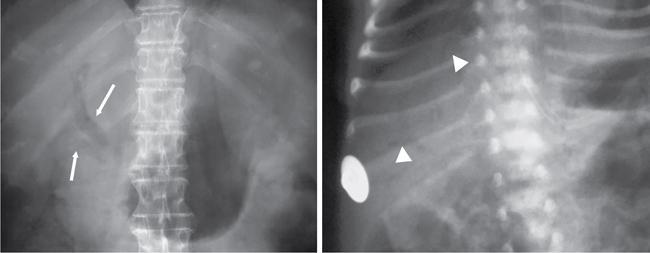

UNDERSTANDING THE ADULT ABDOMINAL RADIOGRAPH: TECHNIQUES AND INTERPRETATION Tanvi Modi Radiography of the abdomen is a common practice for the evaluation of abdominal organs. The anatomy and pathology of digestive, hepatobiliary and genitourinary systems can be assessed using radiographs, either as a stand-alone practice or as a primary imaging modality followed by contrast studies, ultrasound or cross-sectional imaging. In addition, abnormalities of the musculoskeletal or integumentary system can also be deduced on the basis of abdominal radiographs. This chapter intends to give an overview on the techniques and positioning in abdominal radiography as well as interpretation of normal and abnormal features. While superior imaging modalities such as ultrasound, computed tomography (CT), magnetic resonance imaging, capsule endoscopy and the likes have taken over abdominal imaging by and large, radiography still holds a pivotal role in certain situations and conditions, such as: The standard abdominal radiograph is taken in supine position and anteroposterior projection. This is also popularly known as the KUB (kidneys-ureters-bladder) radiograph. Previously, supine as well as erect radiographs were performed in all patients; however, this is not commonly done due to high-radiation dose. For all indications of abdominal radiography, including acute abdomen, supine radiographs are sufficient in terms of radiographic diagnosis, with the exception of perforation for which an erect chest or lateral decubitus radiograph can be performed if there is clinical suspicion. Patient should lie supine on the imaging table with median sagittal plane at right angles to the table and coincident with the midline of the table (Fig. 7.1.1.1). The body is divided into equal right and left halves by the median sagittal which passes through the sagittal suture of the skull. Pelvis should be adjusted so that the anterior superior iliac spines are equidistant from the table top. Gonadal shields, in the case of male patients, should be placed with the upper edge of the shield at the level of pubic symphysis. Although rarely used for female patients, these should be positioned between the anterior superior iliac spines and the pubic symphysis. The centre point of the image receptor should be approximately located at a point 1 cm below the line joining the iliac crests. The X-ray beam should be in a vertical direction, perpendicular to the table top and image receptor at the centre point. Collimation should be such that the soft tissue and subcutaneous region along lateral aspects of the abdominal cavity should be covered within the image. Also, the superior extent involving diaphragm and inferior extent involving the inferior pubic rami is important to look for any lower chest pathologies or any inguinal hernia. 35 × 43 cm (14 × 17 inches) in portrait orientation. On an average, abdominal radiograph exposes a patient to a dose of approximately 1.5 mSv, which is equivalent to 75 chest radiographs or 1/6th dose of a standard CT of the abdomen. The entrance skin dose is approximated to be 4 mGy. At such an effective dose, the additional lifetime risk of fatal cancer is 1 in 30,000. The exposure time is kept short. Patient is asked to exhale completely and hold their breath, with exposure taken at this point of full expiration to ensure imaging of abdominal organs in their natural positions. Modifications of this technique can be made depending on patient habitus and clinical condition. Kilovoltage peak (kVp) should be set to allow adequate visualization of abdominal soft tissue structures as well as semiopaque renal and biliary calculi. Average kVp is set at 70–85 kV. 102 cm (40 inches) Grids are commonly used to reduce scatter radiation. Placement of side marker on the image receptor at the time of radiographic exposure is essential. Bowel pattern depiction should be such that there is minimal lack of sharpness. Standard guidelines for abdominal radiography dictate that the radiograph should extend from the diaphragm up to the level of inferior pubic rami and must include the lateral abdominal wall musculature. The abdomen is divided into four quadrants on the basis of two perpendicular lines (Fig. 7.1.1.7). The vertical line passes through the mid sagittal plane and crosses the umbilicus and symphysis pubis. The horizontal line is a transverse line across the umbilicus at 90 degrees to the vertical line and is situated at the level of L4–L5 intervertebral disc. The quadrants are as follows: Another division system is dividing the abdominopelvic cavity into nine regions using two vertical and two horizontal planes (Fig. 7.1.1.8). The vertical planes, also known as the right and left lateral planes, are parallel to the midsagittal plane between midline and anterosuperior iliac spines on either side. Of the two horizontal planes, the upper transpyloric plane is at the level of lower border of L1 and the lower transtubercular plane is at the level of L5. The nine regions are: On a standard radiograph, the exposure should be such that the stomach, bowel loops, outlines of liver, spleen, kidneys, psoas muscles should be well identified. Also, lumbar transverse processes should be seen. Arch of the pubic symphysis should be visible to evaluate bladder region. A well-centred film without rotation will demonstrate bilaterally symmetrical lower ribs, iliac wings, ischial spines and obturator foramina. Different structures seen on an abdominal radiograph can be classified into five basic densities: Identification of different structures depends on the relative degree of contrast between their densities. The demarcation is clearer in chest and is diminished in abdomen due to relative similar soft tissue density of various structures. On a normal radiograph, relatively large amounts of gas in stomach and colon with minimal small bowel gas can be seen. Further, colonic gas can vary from negligible to extensive, mimicking obstruction pattern; however, usually the gas is enough to delineate colonic haustral pattern. Faecal matter gives a mottled appearance to colonic gas. Short-air fluid levels on an erect radiograph may be seen even in normal cases. The normal appearance of small bowel loops on an abdominal radiograph follows the rule of threes: Stomach is seen in the left upper quadrant and is visualized when distended with air. It is commonly seen extending from T11 to L2 level. Common feature identifying the stomach is the fundal gas which is usually seen as an air fluid level within the gastric lumen. Small bowel loops are distributed to the centre of the abdominal cavity and large bowel loops are peripheral. Duodenum is predominantly situated in right upper quadrant. It extends to left upper quadrant in the region of duodenojejunal flexure. Jejunum occupies the left upper and lower quadrants and is easily identified due to the presence of thick, numerous, closely spaced valvulae conniventes (Fig. 7.1.1.9A). The ileum occupies both lower quadrants and extends into right upper quadrant. Ileum has few and less prominent valvulae as compared to jejunum (Fig. 7.1.1.9B). Ascending and descending colon are retroperitoneal and have relatively fixed positions along lateral aspect of the abdominal cavity on either side. Transverse and sigmoid colon, on the other hand, may have a variable position due to their mobility along mesocolon and redundant pattern. These can be identified with confidence on account of haustrations and faecal matter (Fig. 7.1.1.10). Haustrations are usually well seen in ascending and transverse colon and poorly delineated beyond splenic flexure. Caecum is in the right lower quadrant, though it may be mobile or pulled up. Rectal gas is usually seen in the midline at the level of pelvis and its presence rules out large bowel obstruction. All these positions may vary due to anatomical conditions such as malrotation or pathological conditions, for example volvulus. Liver, spleen and renal outlines cannot be completely traced with precision due to the overlap by bowel loops. On a frontal projection, the liver appears as a triangular structure occupying right and left hypochondrium and epigastric region. Occasionally, the right lobe may be seen extending lower than the right renal shadow. This is a normal variant known as Reidel’s lobe. Gall bladder is situated in the posterior and inferior region of the liver and any pathology of the gall bladder should be looked for in this region. On a lateral radiograph, the gall bladder is anterior to the midcoronal plane. This helps in distinguishing gall bladder calculi from renal calculi, which will be more posteriorly situated. Spleen is seen in left upper quadrant/left hypochondrium, flushed to left lower ribs and left hemidiaphragm. Pancreas is present in the epigastric region (right and left upper quadrants) and is usually not identified in the absence of a pathology. The kidneys are bean-shaped retroperitoneal organs which are seen on either side of the vertebral column and lateral to psoas muscles. Due to the presence of liver on the right side, this kidney is slightly lower in position as compared to its contralateral counterpart. The visualization of kidneys on radiographs is facilitated by the surrounding fatty capsule. Kidneys lie between T11–12 and L2 level, with left kidney 1 cm higher than the right. Psoas muscle shadow can be normally seen along lateral aspect of lumbar spine bilaterally and is mildly concave (Fig. 7.1.1.11). Abdominal wall muscles are not routinely assessed on radiography; however, inclusion of lateral abdominal wall (muscles as well as subcutaneous plane) is a must while performing radiography. The flank stripe or the properitoneal fat stripe is a fat density linear concavity seen along lateral abdominal wall (Fig. 7.1.1.11). It is bound by the paracolic gutters and air-filled ascending and descending colon. All the solid organs in the abdomen are identified due to the fat density outlining them. Distortion of these fat lines helps in identifying organomegaly or focal mass lesions. The dome of urinary bladder is outlined by fat, which aids in differentiating its density from other soft tissue structures of the pelvis. Not all calcifications seen on abdominal radiograph are abnormal. Some may depict age-related changes such as vascular calcifications involving abdominal aorta, pelvic vessels, splenic artery in the region of left upper quadrant. Within the pelvis, phleboliths may be seen and mistaken for urinary calculi. Assessment of lumbosacral spine, iliac bones and femoral heads can be made on the basis of plain radiography. Degenerative changes may be commonly seen. Lower ribs can also be evaluated for pathologies. Dilated small bowel loops with rounded soft tissue density in midline over umbilical region suggests obstruction secondary to umbilical hernia. Pneumoperitoneum must be looked for in all cases of acute abdomen. While erect chest and left lateral decubitus radiographs can detect even 1 mL of free air, there are multiple signs on supine radiograph to suggest this diagnosis, for example Rigler’s sign, falciform ligament sign, football sign (Figs. 7.1.1.24 and 7.1.1.25). Retroperitoneal perforation may demonstrate air outlining psoas muscles and retroperitoneal organs. Small amount of free air may persist in the abdominal cavity up to 3 weeks after surgery, although it usually resolves within a week. Clinical history is important in such cases. Air foci within the bowel wall may represent bowel ischaemia/strangulation. Linear gas patterns in right hypochondrium may be due to two causes, that is pneumobilia and pneumoporta. The former can be seen normally postbiliary surgery, sphincterotomy, ERCP or in the case of abnormal fistulous communication between bowel and biliary tree (Fig. 7.1.1.26A). Pneumoporta (Fig. 7.1.1.26B) is a red flag and warrants further investigation to look for conditions such as mesenteric ischaemia and toxic megacolon. Pneumobilia is more centrally located whereas air shadows in pneumoporta are seen reaching up to periphery of liver. Air foci over renal shadows (Fig. 7.1.1.27), gall bladder or pancreas, in the absence of recent procedural history, suggest fulminant infection and mandate urgent intervention. Central midline calcific foci between T9 and T12 vertebrae can be attributed to calcific pancreatitis (Fig. 7.1.1.28). In the left upper quadrant, areas of calcification seen involving a shrunken spleen may be seen in autosplenectomy. In right upper quadrant, calcified gall stones may be seen. These tend to be small, multiple, uniformly circumscribed and ring-like in appearance with central translucency (Fig. 7.1.1.29A). Mercedes Benz sign, a triradiate pattern of gas lucency, is associated with gallstones. In contrast, renal calculi are more commonly solitary, irregular, of homogenous density, conform to renal calyceal or pelvic outline (Fig. 7.1.1.29B) and are sometimes of staghorn configuration. On lateral view, the gall stones are more anteriorly located as compared to renal calculi, which may be partly superimposed on lumbar vertebrae. Ureteric calculi tend to overlap bony structures such as lumbar transverse processes (Fig. 7.1.1.29B) or sacroiliac joints. Extensive or patchy, curvilinear calcification of gall bladder wall is known as porcelain gall bladder which is often associated with malignant transformation. Calcification involving adrenal glands may be secondary to infection or haematoma, or a congenital condition known as Wolman’s disease where there is bilateral involvement. Discontinuous discrete midline tram track calcification in the abdomen may indicate atherosclerotic changes in abdominal aorta and branch vessels. However, when the calcification is in a globular pattern and seen below the level of L2 vertebra, aortic aneurysm should be suspected (Fig. 7.1.1.30). Appendicoliths, though not commonly seen, may sometimes be detected in right iliac region. Pelvic calcifications: vesical calculi, distal ureteric or vesicoureteric junction calculi, calcified fibroids, ovarian dermoid with tooth-like calcifications (Fig. 7.1.1.31) may be the cause of abdominal pain and should be diligently looked for. Vesical calculi are usually more large and central in location whereas calcification due to fibroids may be more lateral. Schistosomiasis is another cause of bladder wall calcification, as is calcification of bladder tumours. Phleboliths tend to be bilaterally symmetrical, with a lucent centre unlike ureteric calculi. While it is believed that phleboliths are located below the level of ischial spines and ureteric calculi above, this is not always true and should be confirmed with CT. Fluid may collect adjacent to properitoneal fat line, forming a linear soft tissue density separating the fat line from the ascending or descending colon. Hellmer’s sign demonstrates medial displacement of lateral edge of liver (hepatic angle), due to fluid collection or ascites. Gross ascites may appear as generalized abdominal haziness or diffuse increased density of pelvis. Abscesses can involve any solid organ and in such cases may be difficult to demonstrate on plain radiography alone. Enlargement of organ or faint gas densities within can be suggestive of the same. In the case of peritoneal abscess, mottled density due to air, fluid and necrotic contents point towards this diagnosis, especially in right iliac fossa in association with appendicitis. Retroperitoneal abscess, similar to any retroperitoneal mass, may cause displacement of retroperitoneal structures (Fig. 7.1.1.32). Subdiaphragmatic abscesses may show concomitant ipsilateral pleural effusion (Fig. 7.1.1.33). These should be differentiated from Chilaiditi syndrome. Fluid and soft tissue lesions present with the same density on radiographs. While it is difficult to characterize the lesion and organ of origin, clues for the same can be provided by organomegaly (Fig. 7.1.1.34), distortion of fat surrounding solid organs, displacement of bowel loops or solid organs. For example, a retroperitoneal lesion may cause anterior or inferior displacement of kidney, a pelvic mass may cause upward displacement of small bowel loops. Different densities such as fat or calcification may help in identifying organ of origin (e.g. fat and tooth densities seen in ovarian dermoid). Convexity of margins of psoas muscle on an abdominal radiograph can be due to haematoma, abscess or intramuscular tumour. Radiographs are performed for the initial diagnosis of foreign body in the abdomen including type, number of foreign bodies, location, size and shape (Fig. 7.1.1.35). Radiolucent foreign bodies such as wood, plastic, chicken bones will not be easily identified on radiography. Low kVp (65–70 kVp) can increase contrast and help identify these objects. In addition to an abdominal radiograph, chest radiography is also performed to exclude aspiration or oesophageal location of foreign body. Ingested or introduced foreign bodies may cause complications such as obstruction, perforation, fistula formation and sepsis. Hence, once their presence is confirmed, follow up radiography must be performed until they are eliminated. One must look for fractures/dislocation injuries involving the vertebrae or pelvic bones, especially after history of trauma. Lucent expansile lesions or sclerotic bony deposits which represent neoplasms, absent pedicle sign in cases of metastasis, metabolic bony changes such as rugger jersey appearance, Paget’s disease, arthropathies such as ankylosing spondylitis with bamboo spine appearance and sacroiliitis (Fig. 7.1.1.36) are some of the conditions which may be diagnosed based on an abdominal radiograph. Overlap of bowel loops over iliac blades may lead to a misdiagnosis of lucent lesions and should be evaluated with caution. Basal pneumonia may be the cause of acute abdominal pain and should be looked for in abdominal radiography. Similarly, pleural effusion, pericardial effusion, calcified pleural plaques, achalasia, interstitial fibrosis are few other findings that can be seen in lower chest on an abdominal radiograph. Basilar atelectasis can give a deceptive appearance of pneumoperitoneum (Fig. 7.1.1.37). Surgical clips, commonly in right hypochondrium after cholecystectomy, drainage tubes, ventriculoperitoneal shunts, femoral line catheters, IVC filters, stents (vascular, renal, biliary) (Fig. 7.1.1.38), stoma bags, contraceptive devices are some structures that may be seen in an abdominal radiograph. Correct knowledge of patient history and normal locations of these structures prevents misdiagnosis. Certain artefacts may be projected upon the radiograph due to surface structures such as trouser buttons, body piercing, sequins over clothing and should not be considered as a pathology. Multiple skin surface nodules in cases of neurofibromatosis, soft tissue focal swellings, such as abscesses, lipomas, haematomas, desmoid tumours and malignant lesions may be incidentally seen on radiography. These can be further evaluated using ultrasound or CT. Subcutaneous emphysema is another finding that may be seen in lower abdominal wall secondary to retroperitoneal perforation or diffusely along abdominal wall in the case of bowel perforation (Fig. 7.1.1.39). Foreign bodies such as bullets and pins may be seen lodged in abdominal wall. A systematic approach to abdominal radiographs is important for accurate diagnosis as follows: Despite the development of newer techniques for imaging of the abdomen, plain radiography still holds an important place in the initial assessment of acute abdomen. Positive and negative findings on an abdominal radiograph can direct further investigation. Ideal positioning, recognition of normal appearances and keen scrutiny for pathologies is a sine qua non for radiologists reading a plain film of the abdomen. OESOPHAGOGRAM Padma V. Badhe, Vikram Reddy, Sultan Moinuddin Shaukatali, Zillani Alam, Ravi Varma, Abhishek Bairy, Dasari Ravikiran, Revati Tekwani, Soniya Patankar, Megha Nair, Gautham Shankar Oesophagogram is the process of obtaining radiological images and simultaneous motion recording to evaluate function and disorders of pharynx, oesophagus and proximal stomach. Oesophagogram is usually done primarily to evaluate dysphagia. Some of the common indications are oesophageal motility disorders, strictures, gastro-oesophageal reflux disease (GERD) and suspected masses. It can also be used to detect uncommon anomalies like vascular rings/slings and aberrant anatomy. It also helps to evaluate further in cases where there is inability to pass upper GI scope. Double-contrast oesophagogram is mainly indicated in early mucosal disease like erosion, polyp, infection and tumours. If a motility disorder is suspected, dynamic technique (e.g. videofluoroscopy) is used for dysphagia or aspirations in cases of stroke, neuromuscular disorders, post head and neck surgery or radiation. Barium oesophagogram is contraindicated in suspected cases of perforation and tracheoesophageal fistula, aspiration, rarely if there is hypersensitivity to barium suspensions. It is also contraindicated in suspected oesophageal perforation where a water-soluble contrast agent is more suitable. However, ionic water-soluble contrast agent is better avoided in cases of aspiration or fistula with airway. The contrast examination of the pharynx is dangerous in cases of acute epiglottitis and must be ruled out on plain radiograph. An 80% w/v barium suspension is used in full column views. However, 200%–250% w/v barium suspensions is usually required for mucosal relief films. The barium sulphate mixture is fed to the patient either by spoon, by glass, or through a drinking straw, depending on its consistency. In videofluoroscopy, the pharyngeal phase of swallowing is usually safer with barium pudding than with thick barium and safer with thick barium than with thin barium. However, if the major abnormality is poor pharyngeal contraction leading to stasis in the piriform sinus (and epiglottic tilt is normal), a thin liquid is safer. Epiglottic motility is better assessed with thin barium because thick barium often obscures the epiglottic tip. Fluoroscopic equipment capable of cine fluoroscopy and capability for rapid sequence spot images (high frame rate) is needed for this examination, Barium suspension, straw, glass, Lead apron and radiation protective equipment. The patients are instructed to fast after midnight before the day of the examination. The pharynx should be made as dry as possible during the examination as high-density barium adheres to dry pharyngeal mucosa. Activities like smoking, chewing gum and lozenges must be abstained before the procedure as they impair barium coating by increasing the salivary secretion. Regular oral medications must be taken with sips of water; however, insulin must be skipped on the morning of examination. The major principles of a good oesophagogram includes mucosal coating, distension and projection. A routine oesophagogram consists of screening of the oral, pharyngeal and oesophageal phases of swallowing, single and double-contrast examination of pharynx, single contrast, double-contrast and mucosal relief views of the oesophagus. In cases of dysphagia, the examination is tailored depending on whether the symptoms are either pharyngeal or oesophageal and initial fluoroscopic findings. If patients’ symptoms are suggestive of oral or pharyngeal disorder then pharynx is evaluated first. Similarly, if patient is suspected to have thoracic oesophageal disease then, double-contrast examination of the oesophagus is performed before the pharyngeal evaluation. During an oesophagogram the positioning of the patient varies according to the type of examination (Table 7.1.2.1).